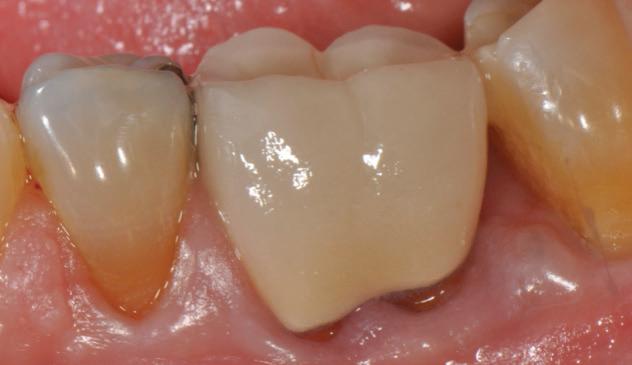

-year follow-up radiographs showed evidence of bone fill. Clinically, maturation of interdental tissue is evident as well.

-year follow up clinical photos are demonstrating stability of bone, lack of facial and minimal interproximal recession.

-year follow-up radiographs showed evidence of bone fill. Clinically, maturation of interdental tissue is evident as well

Stability of the bone radiographically is evident as well.

-year follow up clinical photos are demonstrating stability of bone, lack of facial and minimal interproximal recession. Stability of the bone radiographically is evident as well.

® did not only enhance the outcome of this challenging case, but ensured its st ability